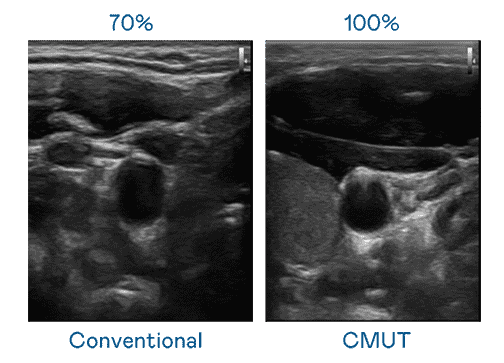

CMUT 技术是一种用电容式微机电元件来产生超音波讯号的技术。。。。与传统 PZT 压电式技术相比,,,CMUT 频宽增加 30%,,更宽频的超音波讯号让影像解析度大幅提升,,,,是实现高影像品质医疗超音波扫描、、、、促进精准医疗发展的关键技术。。。

大频宽带来超清晰影像

超音波影像的解析度高低,,,,首先取决于探头能发出的讯号频宽。。。。尊龙集团 CMUT 可提供高清晰的超音波讯号,,,,提供高频宽、、高灵敏度、、、、影像纹理细节更高的超音波影像,,,,协助医护人员缩短影像判读时间及利用精准的医疗影像进行诊断。。。